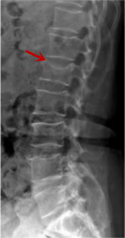

利器一:X線/DR

腰椎X線片作為最基礎(chǔ)的影像檢查手段,利于X線穿透人體組織后成像,以其快捷、直觀、價格低廉的特點,X線檢查主要包括腰椎正側(cè)位、雙斜位以及過伸過屈位。主要用于觀察腰椎骨骼的情況,如椎體是否有骨折、骨質(zhì)增生程度、生理曲度的變化、椎體移位的情況等。然而,X線檢查也有它的局限性,無法判斷是骨折的新舊,對于椎體內(nèi)部結(jié)構(gòu)和周圍肌肉韌帶組織(如脊髓神經(jīng)、椎間盤、韌帶等)的顯示不佳,另外X線作為有輻射檢查,孕婦及嬰幼兒謹(jǐn)慎選擇。

箭頭提示腰3椎體滑脫